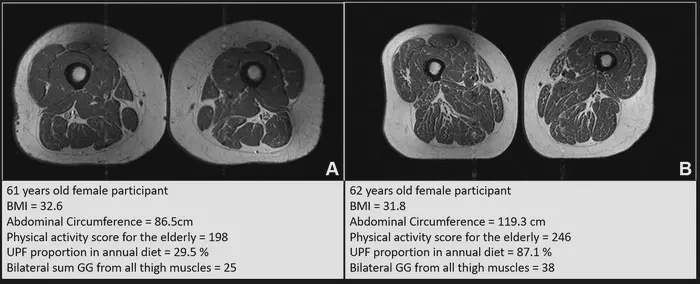

Eating ultraprocessed foods is linked to a higher amount of fat in the thigh muscles, researchers at the Radiological Society of North America warned in a recent study. And that’s true regardless of how many calories you consume, how much you work out and what your genetic history is.

Using MRI imaging and data from the decade-long Osteoarthritis Initiative, the researchers looked at the thighs of more than 600 adults who had a diet that was 41 percent ultraprocessed.

The scans showed how much fat each person’s muscles stored – and that people with poorer diets were worse off.

-a-61-year-old-female-and-(B)-a-62-year-old-female-(IMAGE).jpeg)